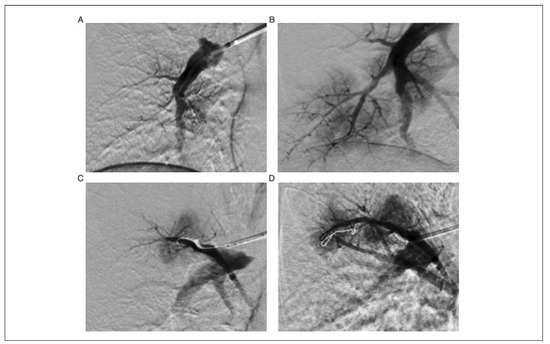

Severe Pulmonary Embolism: Surgical Aspects

by Oliver Reuthebuch

Severe pulmonary embolism is a life-threatening disease requiring a wellbalanced therapeutic approach. It is of upmost importance to differentiate between acute pulmonary embolism and chronic pulmonary embolism in this setting. The management of acute embolism is predominantly carried out by the internal specialist, [...] Read more.

Severe pulmonary embolism is a life-threatening disease requiring a wellbalanced therapeutic approach. It is of upmost importance to differentiate between acute pulmonary embolism and chronic pulmonary embolism in this setting. The management of acute embolism is predominantly carried out by the internal specialist, whereas the therapy of chronic pulmonary embolism is in the domain of the surgical community. Acute, untreated pulmonary embolism has a mortality of >30%, with two thirds of deaths occurring within the first 60 minutes. It is the most common cause of death without a prior clinical diagnosis because of its vague and nonspecific clinical symptoms and undefined laboratory parameters. The nature of chronic pulmonary embolism is different since it is based on recurrent pulmonary emboli without complete resolution. Five-year survival is pressure dependent, with a mere 10% survival rate in patients having a mean pulmonary arterial pressure of more than 50 mm Hg. It has an incidence of up to 3.8% in survivors of acute pulmonary embolism, as well as an incidence of >10% in patients with recurrent embolism. There are various treatment options for acute pulmonary embolism based on the haemodynamic stability or instability of the patient. If the patient is stable, anticoagulation is to be administered with a potential subsequent implantation of an inferior vena cava filter. If the patient is unstable, thrombolytic therapy has to be considered first. If this fails, mechanical embolectomy or even surgical embolectomy should be taken into account. Patients with chronic pulmonary embolism should be treated surgically with a bilateral endarterectomy of the pulmonary arteries. This is the standard and recommended treatment. The role of the emerging percutaneous pulmonary angioplasty is not yet defined and needs further evaluation. Patients suffering from acute or chronic pulmonary embolism should be transferred to a certified centre. There, specialists decide on the appropriate treatment with potential implantation of life-supporting systems (e.g., extracorporeal membrane oxygenation). Full article

Show Figures

Figure 1